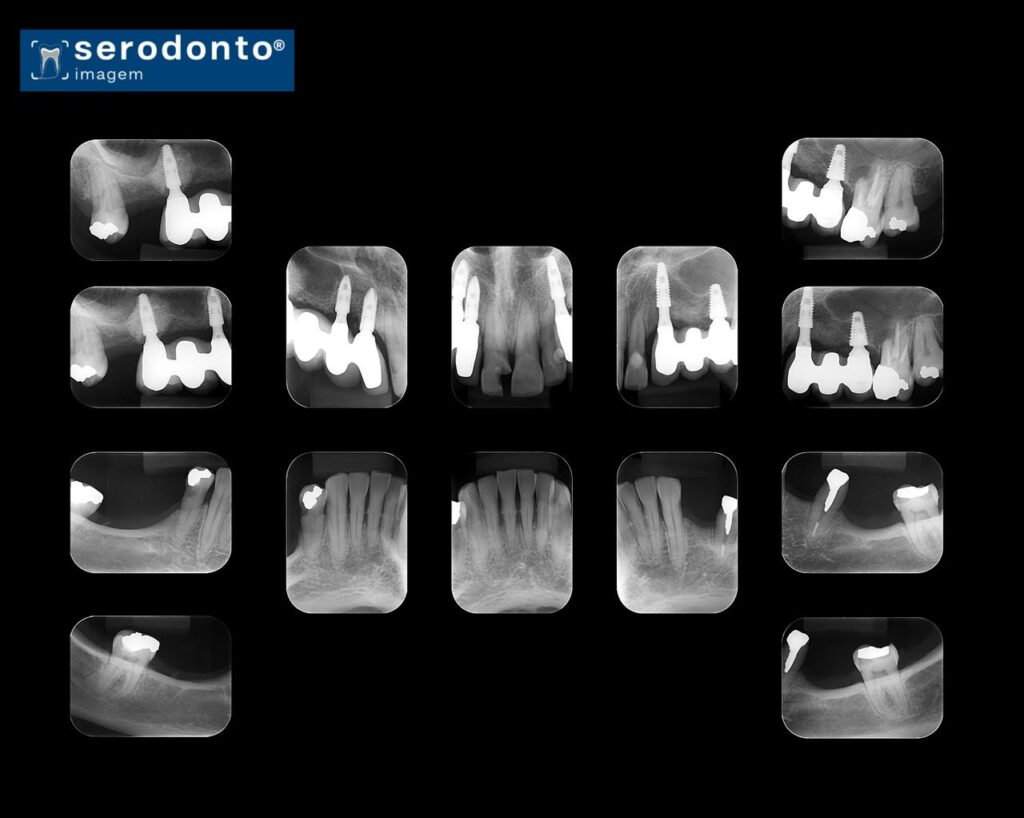

O exame periapical completo envolve a captura de múltiplas imagens periapicais, proporcionando uma visão abrangente da saúde bucal.

Avaliação detalhada de toda a arcada dentária.

Identificação de lesões em diferentes estágios.

Planejamento de tratamentos restauradores e endodônticos.

Monitoramento de condições periodontais e ósseas.

Cobertura completa das estruturas dentárias.

Imagens de alta qualidade para diagnóstico preciso.